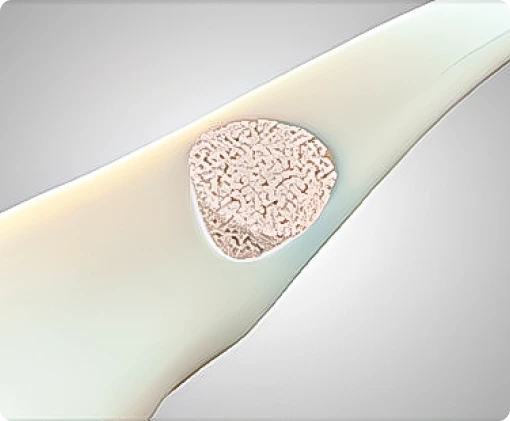

Os grânulos bioativos (granulometria 0,09 a 0,71 mm) são compostos unicamente por elementos presentes naturalmente no tecido ósseo (Ca, P, Na, Si, O).

A liberação desses íons durante a reabsorção dos grânulos de vidro bioativo permitirá a formação à superfície de uma camada de hidroxiapatita carbonatada, cuja composição e estrutura são similares à fase mineral do osso.